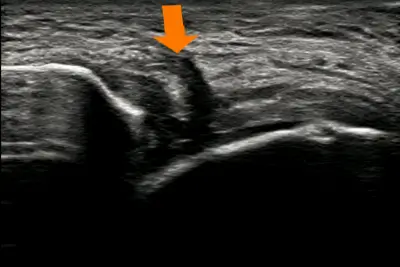

• 前距腓靭帯のエコー像 損傷前距腓靭帯 損傷

足関節捻挫では、多くの場合は外果(外くるぶし)の前方や下に腫れや痛み、皮下血腫がみられることがあります。診断にはレントゲン像で骨折の有無の確認や超音波検査装置(エコー)での靭帯損傷の評価をして重症度を判定します。重症のⅢ度の足関節捻挫では軟骨損傷などの他の損傷を伴っていることもあり、必要に応じてMRIを撮影することもあります。